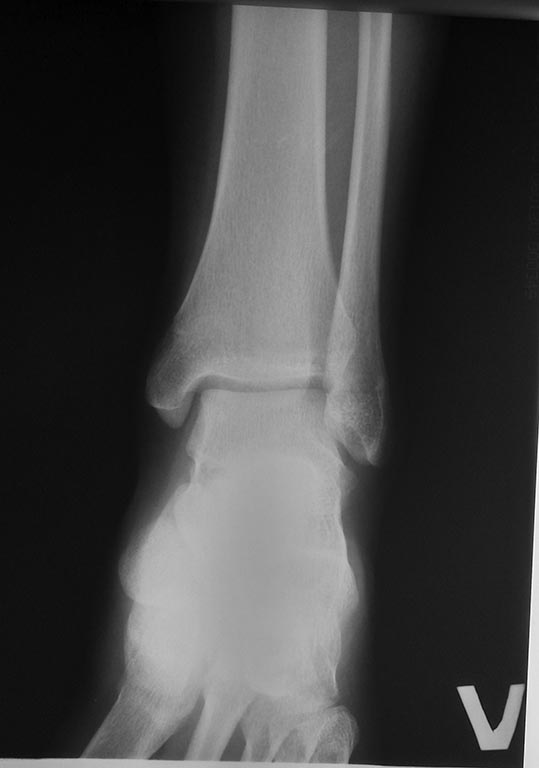

Хотим посоветоваться с Вами по тактике лечения девочки 13 лет.

К нам обратилась девочка с жалобами на боли в правом коленном суставе и

стопе. Со слов боли в течение последних 6 месяцев, усиливаются после

длительной ходьбы. В покое не беспокоят либо быстро купируются приемом

НПВП. Ночных болей нет. По месту жительства выполнялись Р граммы

коленных суставов и УЗИ. Какой либо существенной проблемы не обнаружено.

При осмотре походка не нарушена. Обращает на себя внимание, справа

несколько больше контурируется головка правой малоберцовой кости. При

пальпации болезненность в проекции, головки малоберцовой кости и

малоберцового нерва. Боли в стопе в области пятки и тыла стопы. Пареза

малоберцового нерва нет, парастезии, расстройств чувствительности нет.

Невролог еще не смотрел. Других видимых и пальпируемых изменений не

обнаружено. Единственное, что можно добавить, несколько увеличена

латеральная лодыжка в сравнении с контралатеральной.

Движения в коленном и голеностопном суставе в полном объеме.

При измерении длины конечностей имеется укорочение правой голени до 1,5

см. При том сама пациентка этого не замечала. Каких либо беспокойств это

укорочение доставляет.При «выпытывании» выяснили, что несколько лет

назад был перелом голени в н/3, лечилась оперативно. Закрытая репозиция,

остеосинтез спицами остеоэпифизиолиза большеберцовой кости в н/3 со

смещением. Нашла выписку. В дальнейшем, каких либо жалоб нет. Пациентка

была на амбулаторном приеме, успел сделать фото имеющихся снимков

телефоном. Рентгенограммы какие есть. Извините.